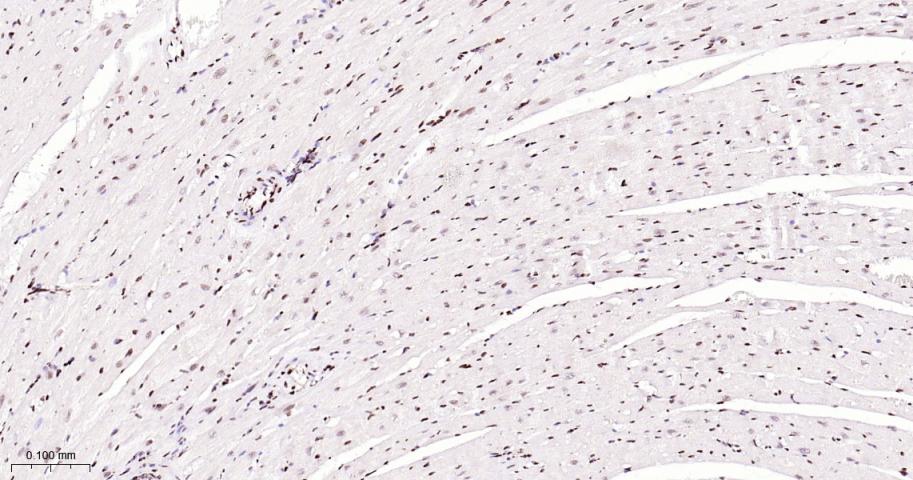

Paraformaldehyde-fixed, paraffin embedded Human Heart; Antigen retrieval by boiling in sodium citrate buffer (pH6.0) for 15 min; The section was incubated with CTBP2? Monoclonal Antibody, Unconjugated (bsm-62448R) at 1:200 overnight at 4°C, followed by conjugation to the bs-0295G-HRP and DAB (C-0010) staining.

Paraformaldehyde-fixed, paraffin embedded Rat Heart; Antigen retrieval by boiling in sodium citrate buffer (pH6.0) for 15 min; The section was incubated with CTBP2? Monoclonal Antibody, Unconjugated (bsm-62448R) at 1:200 overnight at 4°C, followed by conjugation to the bs-0295G-HRP and DAB (C-0010) staining.

Paraformaldehyde-fixed, paraffin embedded Mouse Heart; Antigen retrieval by boiling in sodium citrate buffer (pH6.0) for 15 min; The section was incubated with CTBP2? Monoclonal Antibody, Unconjugated (bsm-62448R) at 1:200 overnight at 4°C, followed by conjugation to the bs-0295G-HRP and DAB (C-0010) staining.